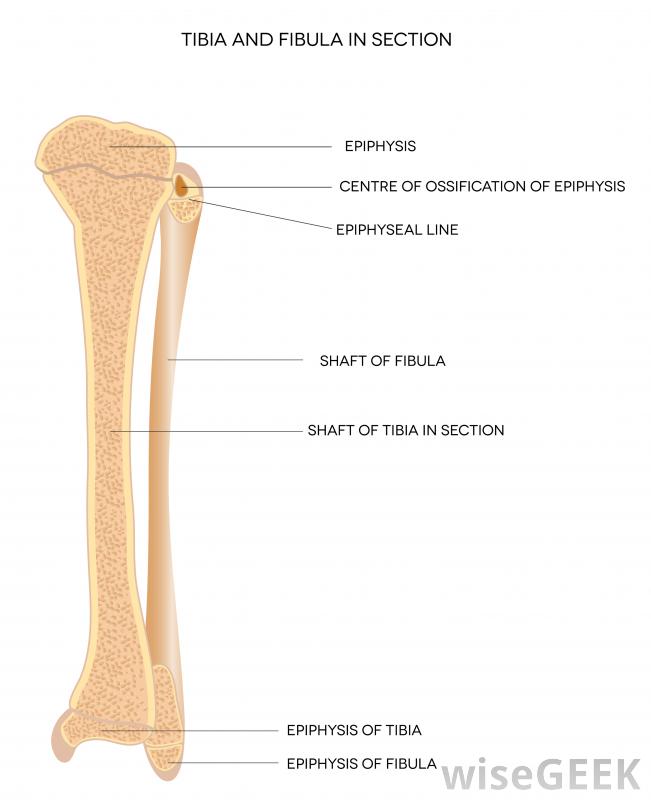

腓骨是小腿較細的長骨。